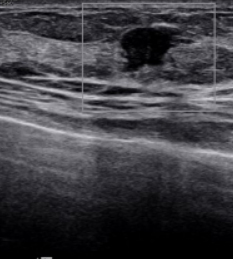

유방초음파는 초음파 검사 시 병원마다 약간의 차이가 있지만 기본 10만 원부터 시작하며 보험 미적용 대상입니다.

하지만 초음파 검사 비용에 건강보험을 적용할 시 약 4~8만 원 정도만 내면 됩니다.(60% 수준 감경) 정확한 금액은 의료기관별로 다릅니다.

검사할 때 건강보험 혜택이 적용되는 기준은 따로 있습니다. 우선 가장 보편적으로 사용하는 흑백 영상 초음파 장비는 건강보험이 적용됩니다. 단, 진단 결과에 따라서 양성이냐 악성이냐 여부에 따라 최종 결정됩니다.

진료의사의 의학 판단에 따라 유방'액와부, 흉벽, 흉막, 늑골 부위에 질환이 의심되거나 이미 갖고 있는 질환으로 인해 경과 관찰이 필요한 경우 의사가 직접 시행한 초음파 검사에 한해 건강보험 적용이 됩니다.